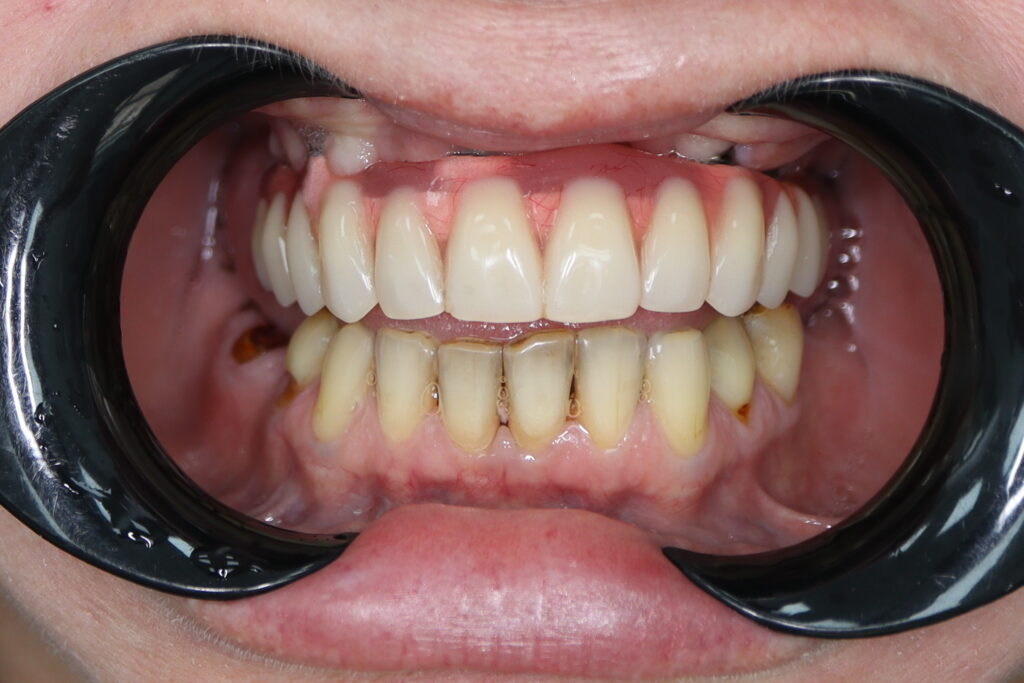

Результаты

результат тотальной имплантации